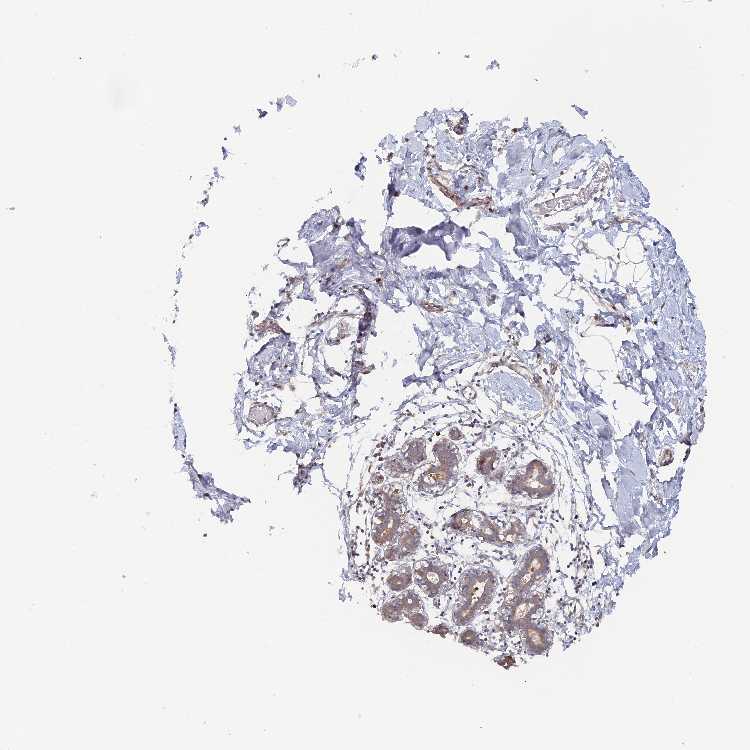

BREAST - Antibody stainingi

Antibody staining in the annotated cell types in the current human tissue is reported as not detected, low, medium, or high, based on conventional immunohistochemistry profiling in selected tissues. This score is based on the combination of the staining intensity and fraction of stained cells.

Each image is clickable and will lead to virtual microscopy that enables deeper exploration of all samples and also displays staining intensity scores, fraction scores and subcellular localization as well as patient and tissue information for each sample.

Antibody HPA043163

Adipocytes Low

Glandular cells Low

Myoepithelial cells Low